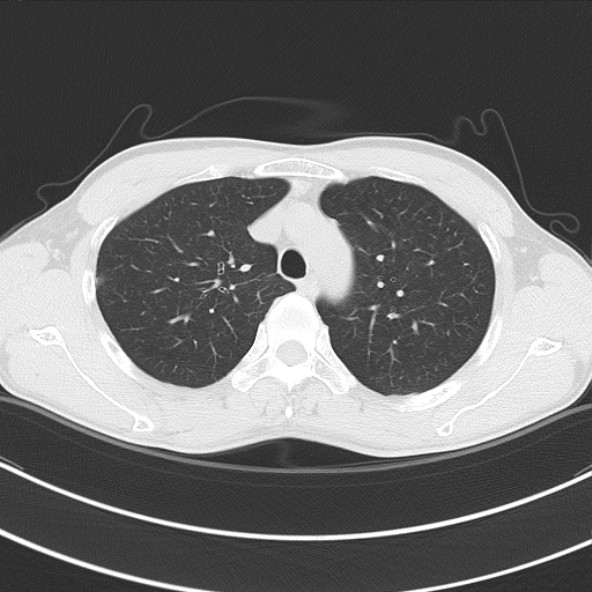

CT52828:肺部小结节及磨玻璃结节,轻度强化

男,47岁,外伤CT发现肺部单个小结节及多发磨玻璃结节,三个月后复查变化不明显,求诊断思路!

右肺中叶外带见磨玻璃结节影,外形欠规整,增强扫描轻度强化。 考虑:恶性结节可能性大。

右肺中叶外带磨玻璃样结节,外形欠规整,轻度强化。考虑:恶性结节可能性大

右肺中叶外带磨玻璃样结节,外形欠规整,轻度强化。考虑:恶性结节可能性大。

右肺中叶外带小结节灶,局部见胸膜反应,恶性病变不能除外。

个人建议:如若其它检查未见异常,建议早期手术。